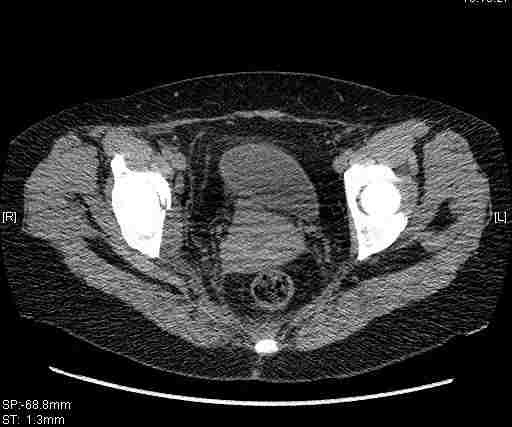

Удалось сегодня вывести пациентку в соседнюю больницу, где есть кт. Срезы сделаны только горизонтальные.